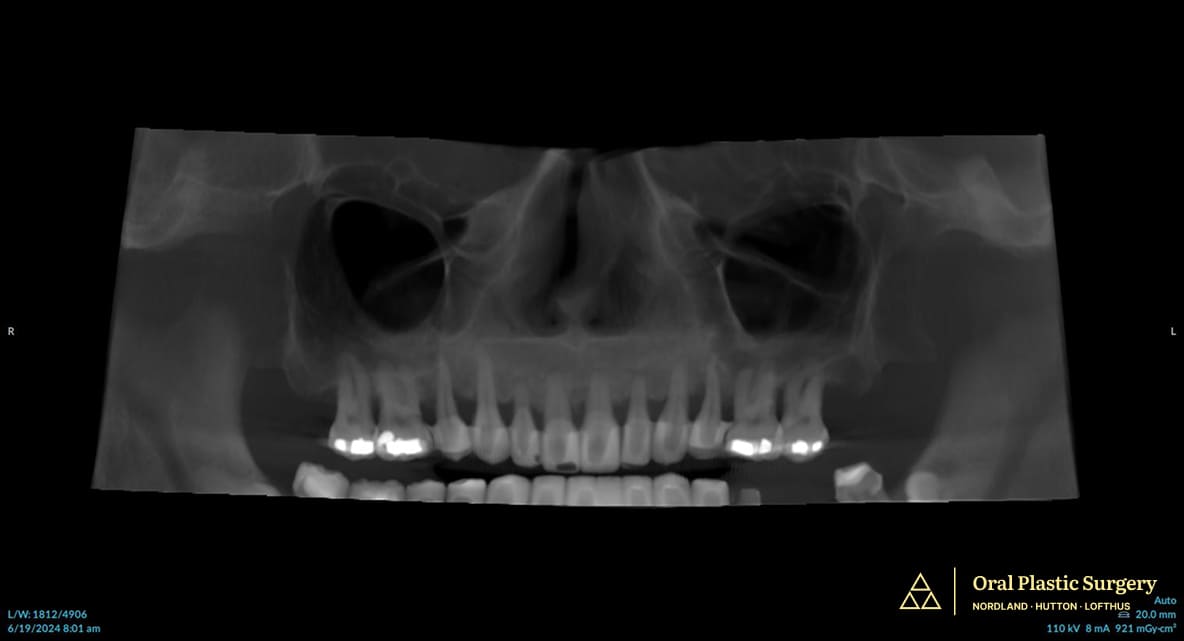

Dr. Lofthus performed a CBCT scan (3D imaging) to evaluate the ridge anatomy and determine whether implant placement was possible.

The scan revealed a common challenge in congenitally missing-tooth cases. Because the tooth never developed, the jawbone in that area never fully formed to normal thickness. Because the baby tooth had been missing for many years, the ridge had become too narrow and deficient for predictable implant placement.

Cone-beam computed tomography (CBCT) is essential in these cases because it reveals bone width, height, and density in three dimensions, information that cannot be accurately assessed from traditional 2D radiographs.

This allows the surgeon to measure the exact ridge dimensions and plan the appropriate volume and positioning of bone augmentation needed to support an implant long-term.